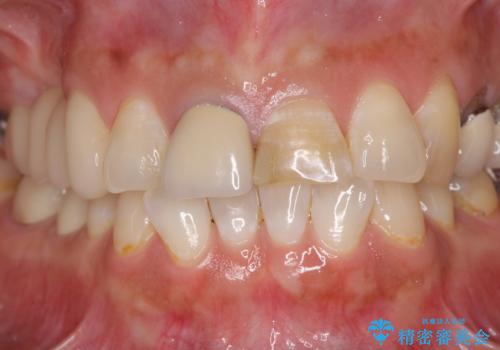

- 上の前歯2本が不調和であることを気にして来院された患者様です。

以前に前歯をぶつけた際、一方は神経を取り除いたためクラウンを装着し、もう一方は神経が残せたため一部修復をしていたとのことでした。

神経は残せていましたが、歯の色の変色が著しく、また広がった大きな形をしていたため、前歯2本をオールセラミッククラウンにて補綴することとしました。